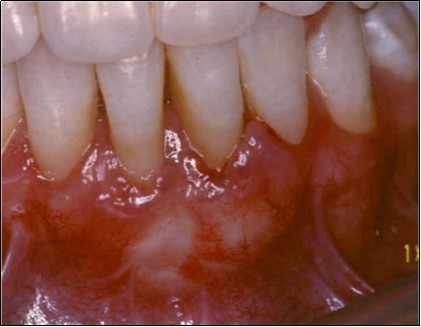

The patient under hard emotional stress that associated with bacterial plaque promoted ANUG with necrosis of alveolar bone and marginal gingival soft tissue in 31 and 41 (Figure 1). The patient was free of systemic disease and was not currently receiving any medication. Initial therapy was carried out using Er-YAG laser, to promote scaling and root planning and oral hygiene instruction. After initial therapy (Figure 2) the surgical method employed consists of the following steps as described by Langer and Langer5.

Figure 2.After initial therapy

After initial therapy